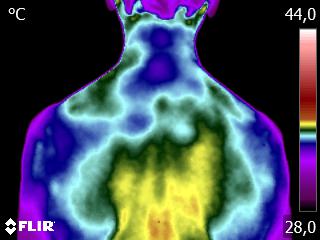

Caros colegas fisioterapeutas e terapeutas ocupacionais, vocês sabiam que, por meio do estudo da Termofuncional, é possível identificar alterações térmicas […]

Caros colegas fisioterapeutas e terapeutas ocupacionais, vocês sabiam que, com o estudo da técnica Termofuncional, é possível identificar alterações térmicas […]